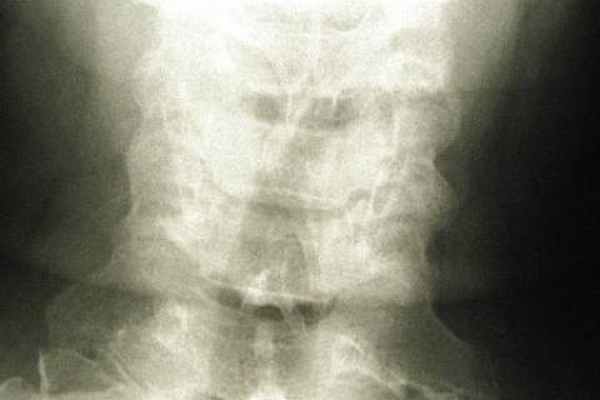

Другим видом аномалии краниовертебрального перехода являются платибазия и базилярная импрессия — вдавление основания затылочной кости и ската черепа в заднюю черепную ямку как таковые либо в сочетании с внедрением краев основания затылочного отверстия, затылочных мыщелков и зубовидного отростка Сц в полость задней черепной ямки. Впрочем, оба вида аномалий Арнольда — Киари и базилярная импрессия часто сочетаются. Диагноз подтверждается рентгенологически: тень зубовидного отростка аксиса определяется выше линии Чемберлена, соединяющей задний край большого затылочного отверстия с задним краем твердого нёба, и выше линии Пити, соединяющей нижние края затылочных мыщелков.

Для постановки диагноза необходимо провести рентгенограмму, основаниями для которой являются симптомы и данные измерений черепа больного. Для уточнения аномалии проводится компьютерная томография шейного отдела спинного и головного мозга. С их помощью точно определяются размеры и расположение патологии, наличие изменений в нервной системе, присутствие злокачественных образований.

Диагноз обычно устанавливается при проведении рентгенографии, КТ или МРТ.